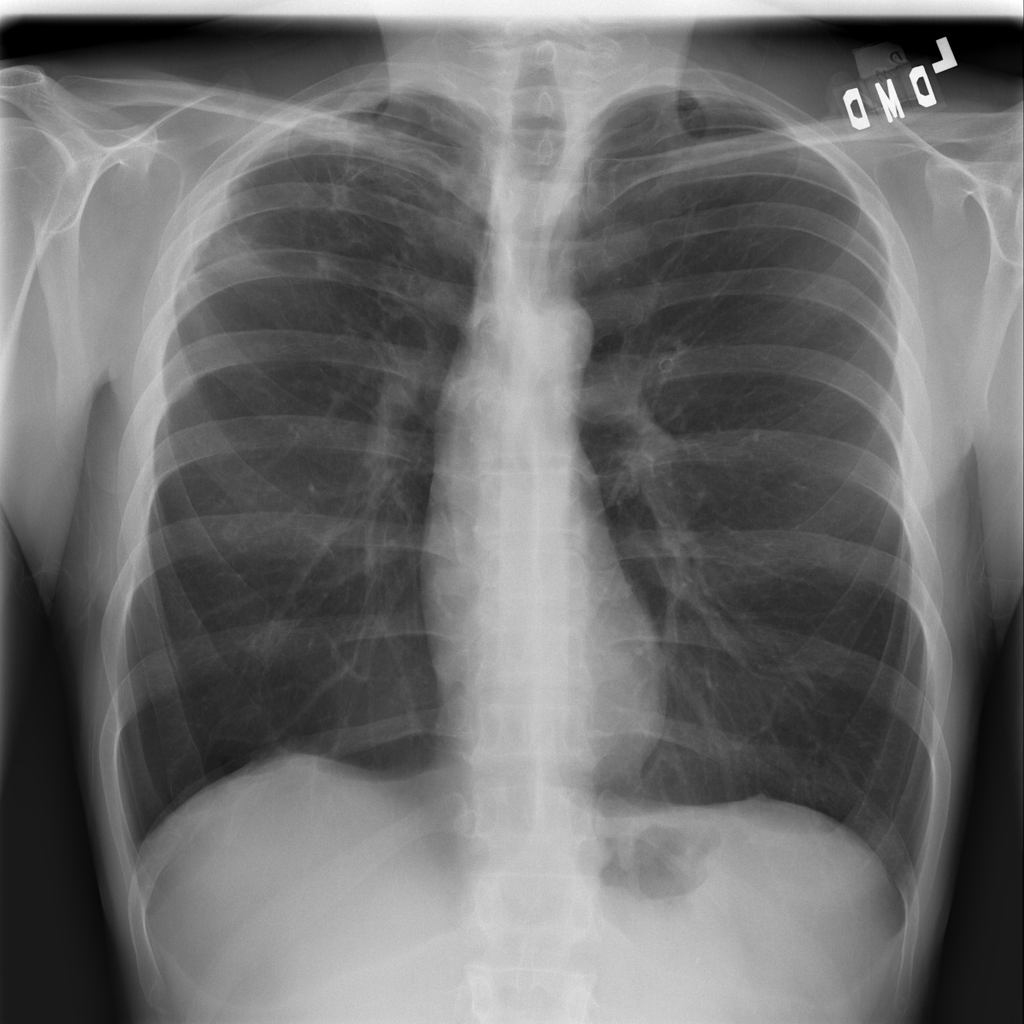

Consolidation

Consolidation refers to air-space filling that makes part of the lung appear denser on imaging.

Showing up to 90 reference images for Consolidation.

PAT-C1A7 · IMG-055Consolidation

PAT-C1A7 · IMG-055

AP